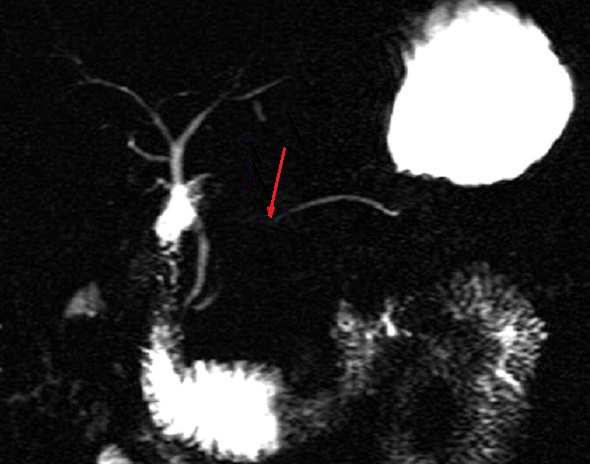

Image radiologique cholangio-Wirsungo IRM

d'une traumatisme du corp pancreas avec aspect

lesionel de rupture du canal pancreatic principale(

fleche rouge) |